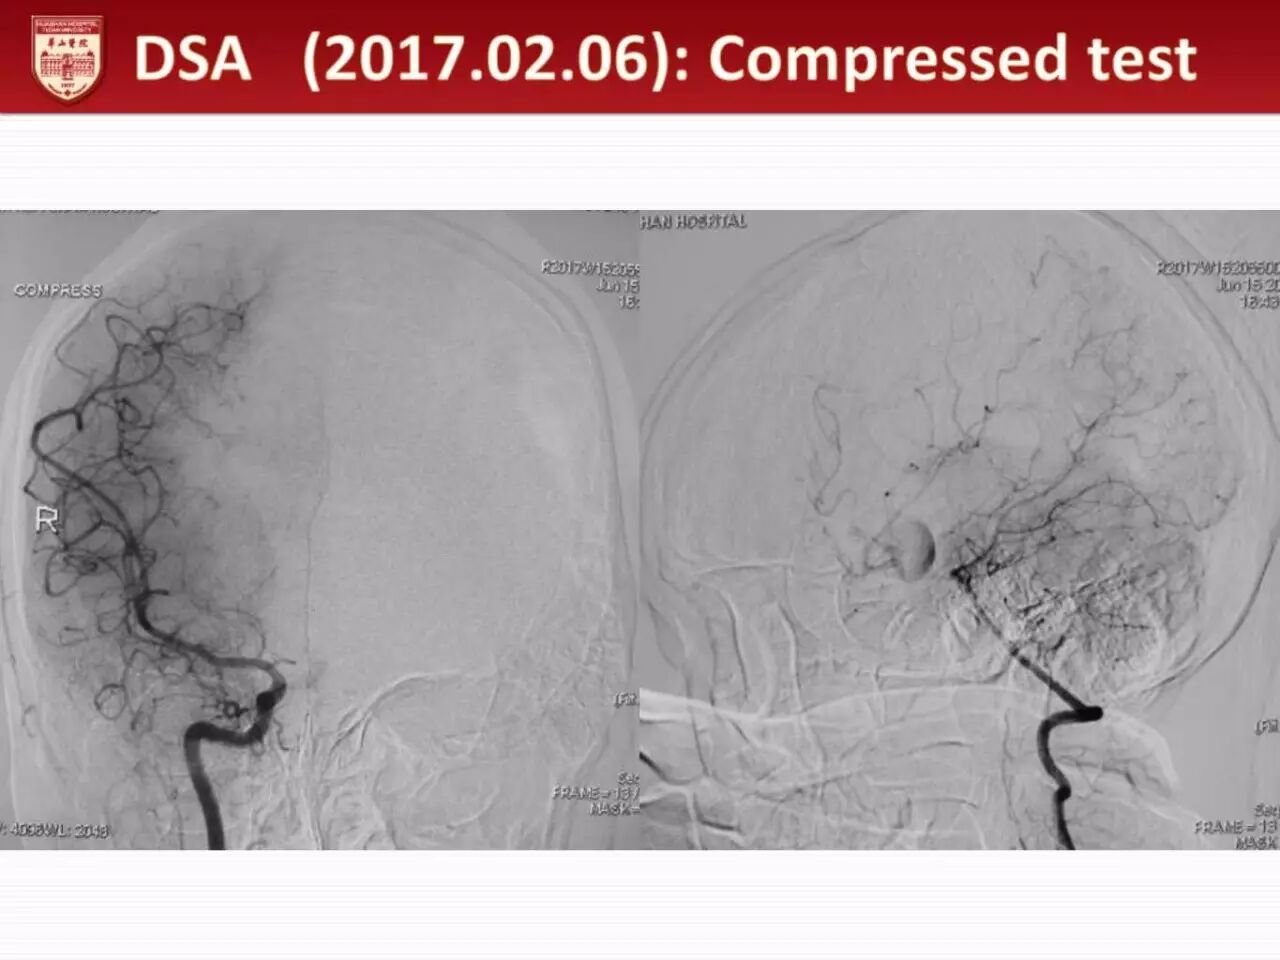

本例是一例女性患者,29岁,因反复头痛头晕检查发现前交通巨大动脉瘤,占位效应明显。视力视野检查发现右眼颞侧偏盲。该动脉瘤巨大且占位效应明显,治疗指征明确。考虑到介入治疗费用较高,且无法解除动脉瘤占位效应,而开颅夹闭不仅能够缓解动脉瘤占位效应,且治疗更加彻底、费用更低,因此经讨论后决定行动脉瘤开颅夹闭术。

从影像资料上看,动脉瘤虽然较大,但瘤壁钙化不明显,因此有塑性夹闭可能。手术在华山医院复合手术室进行,由顾宇翔教授主刀。患者经右侧额颞入路,开颅后首先经侧裂暴露右侧A1,因瘤体较大,无法完全暴露动脉瘤形态,遂经纵裂逐渐解剖暴露动脉瘤体,右侧A1、A2,前交通和对侧A2,对侧A1不明显。动脉瘤瘤体巨大,无法暴露整个动脉瘤形态,但瘤壁无明显钙化,因此决定临时阻断右侧A1、A2及对侧A2后抽吸瘤体,迅速解剖瘤体结构,先用一枚支架夹闭部分瘤体,随后用四个90度弯开窗夹依次串联夹闭动脉瘤颈,并重新对前交通动脉进行塑性。